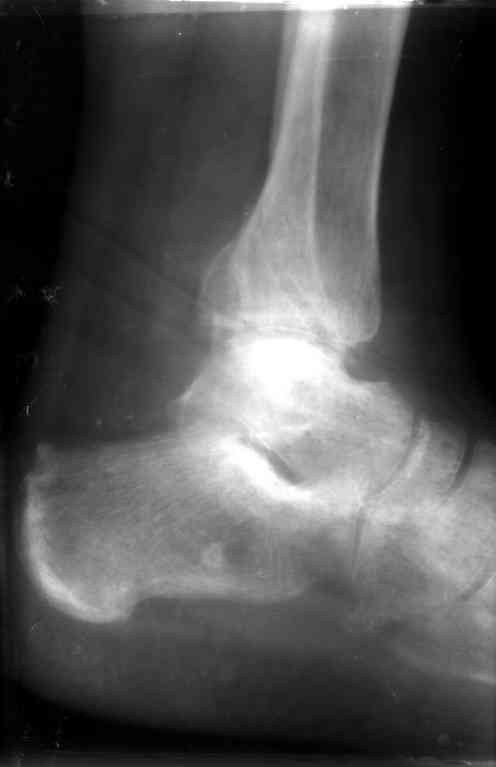

Перелом обеих лодыжек и з/края б/б кости с вывихом стопы,new |

Ув. коллеги, я уже сообщал об этом случае недавно. Металлоконструкции удалены через 7 недель с момента травмы, после чего еще месяц иммобилизации, осторожная дозированная нагрузка. Спустя 3,5 месяцев имеем следующее. Что порекомендуете? С ув. Sergey A. Melashenko ул. Кирова 88-А, г. Приморск, Запорожская обл., 72100, Украина

Ув. Максим. Движения в суставе в полном объеме, беспокоят выраженные боли в суставе, сохраняется отек. Осевая наргрузка болезненна, особенно

в проекции синдесмоза. Похоже вся проблема в синдесмозе. Может обождать, пока окрепнет наружная лодыжка и провести операцию, как при застарелом

повреждении синдесмоза (болт-стяжка или что-нибудь поновее)

Склоняюсь к мнению, что тактика лечения такой больной была не совсем адекватна, необходимо было в первые 2-3 суток (после проведенной репозиции) произвести остеосинтез по АО с позиционным винтом или даже

ургентно, в первые часы после травмы.